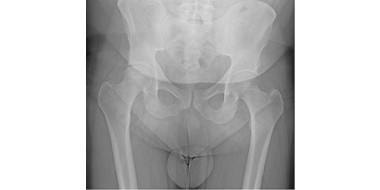

• Een man met knieklachten door een heupafwijking

Knieklachten kunnen een uiting zijn van een aandoening van het heupgewricht. Bij het lichamelijk onderzoek van patiënten met knieklachten moet altijd het heupgewricht worden onderzocht. …